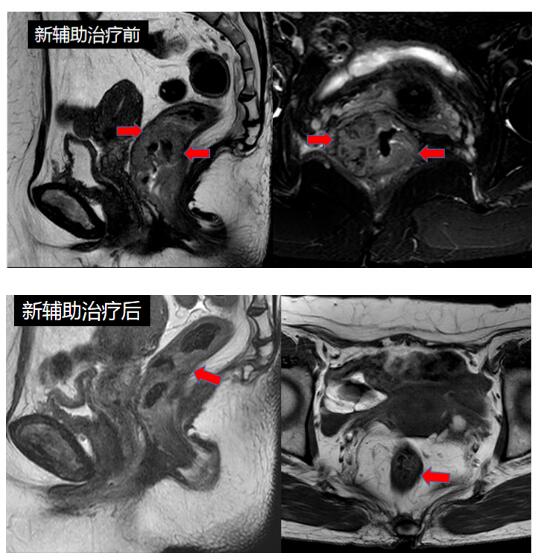

经术前4周期规律新辅助化疗后,患者肿瘤明显退缩,区域淋巴结基本消失,普外科·胃肠外科主任彭有军认真分析病情,结合直肠指检、直肠磁共振、结肠镜、肛门镜等结果,认为肿瘤未浸润肛门外扩约肌,且肛门功能良好,已达到手术条件,且可尝试保留肛门。经充分术前准备,2022年12月5日,手术如期进行,借助先进的3D腹腔镜设备和器械,通过几个不到1cm的小孔,充分发挥腹腔镜下对盆腔解剖的优势,彭有军主任手术团队依靠丰富的经验和娴熟的技巧,顺利完成了手术并成功保肛。整台手术出血量仅有20ml,手术达到了根治性切除,保证了切缘安全,同时尽可能保留了完整的肛门外括约肌和肛管,极限状态下保住了肛门和控便功能。